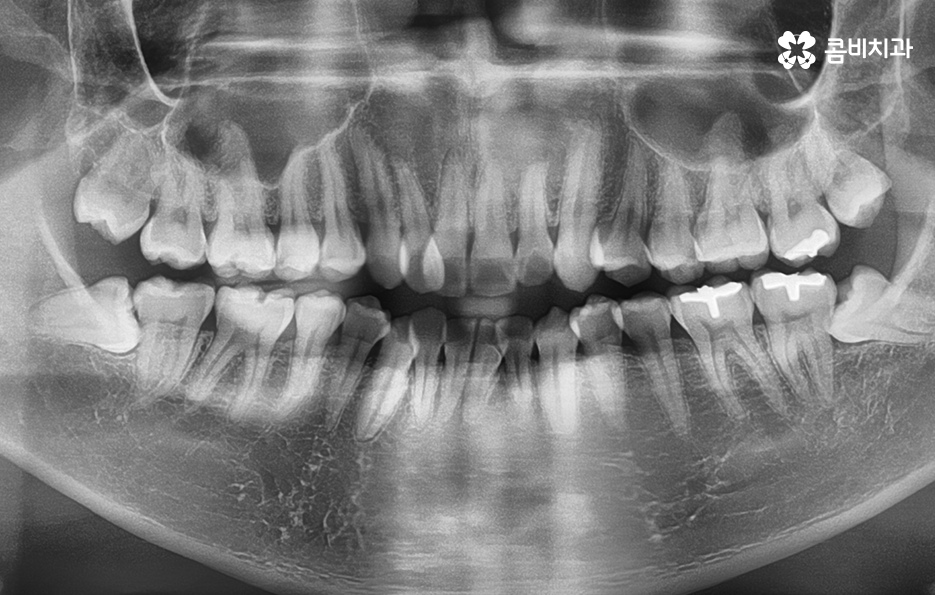

덧니의 주된 원인이 턱뼈가 좁아서 치아가 자랄 공간이 부족하다 보니 덧니의 형태로 영구치가 자라는 경우가 많다 보니 전체 치열을 가지런하게 재배열 하기 위해서는 충분한 치아의 이동 공간이 필요하고 치아의 이동 공간을 확보하는 방법으로 주로 소구치 즉 작은 어금니를 발치하는 발치교정 방식이 보편적으로 많이 활용되고 있는데요

치아를 이동시키기 위한 공간 확보 방법은 악궁확장이나 어금니를 후방으로 이동시키는 방법, 치간 삭제와 같이 비발치적인 치료 방법도 있으나 비발치적인 교정 방법으로는 한계가 있고 오히려 비발치 뻗침과 같은 부작용이 예상되는 경우에는 소구치 발치를 통한 발치 교정 방법이 적합한 경우 많기 때문에 결론부터 말씀드리자면 1:1 맞춤형 치료를 하는 것이 맞으나 덧니가 심할수록 발치교정이 적합한 경우가 좀더 많다고 볼 수 있어요

치아교정을 위한 발치교정 과정은 대부분 소구치 라고 불리는 첫번째 작은 어금니를 발치하게 되며 좌우, 위 아래 총 4개의 소구치를 발치한 후에 덧니가 재배열 될 수 있는 공간을 만들기 위하여 우선 송곳니를 후방으로 이동시키고 있어요